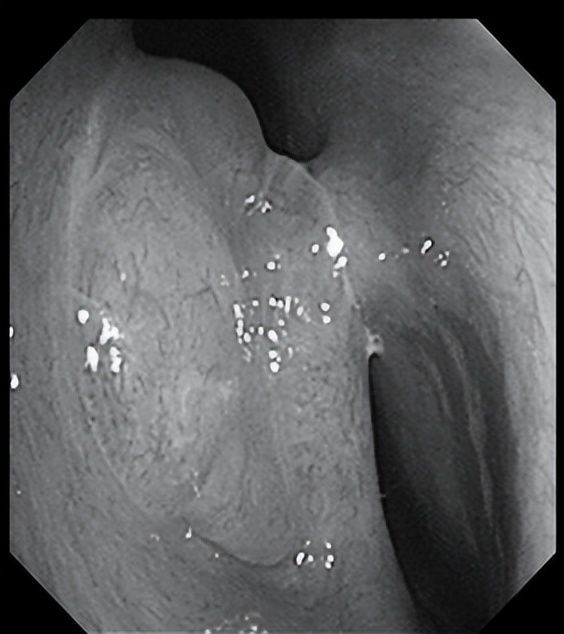

电子喉镜检查

左侧鼻腔

右侧鼻腔

鼻咽部

声门